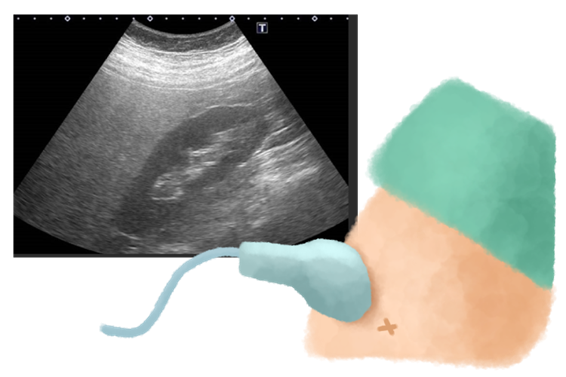

- 腹部超音波(エコー)検査:痛みや被曝の心配がなく安全に、肝臓の形や脂肪の蓄積具合を視覚的に評価できます。脂肪が多いほど肝臓は画像上で「白っぽく」見えます。エコー検査では、脂肪肝の重症度を「軽度」「中等度」「高度」の3段階で評価し、重症度が高いほど進行リスクが高い可能性を示唆します。